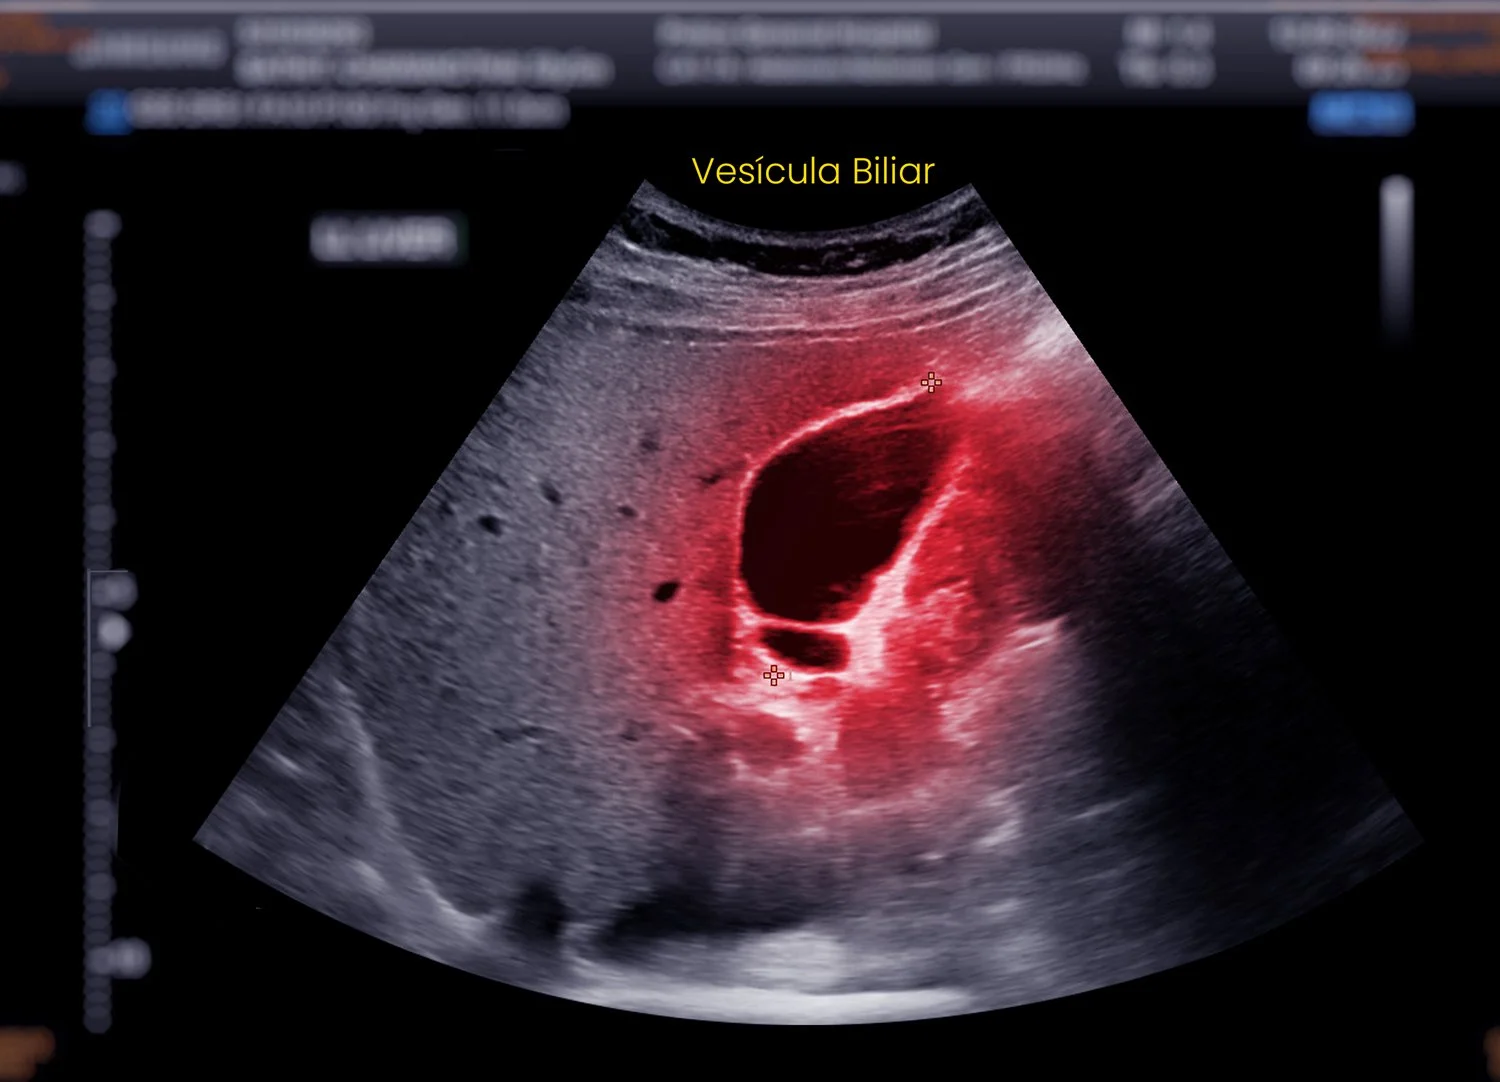

Cirugía Vesícula Biliar

La cirugía de vesícula se recomienda cuando existen piedras en la vesícula (cálculos biliares) que provocan dolor, digestiones pesadas, náuseas o inflamación. Estas piedras pueden obstruir los conductos biliares y causar cólicos biliares intensos, vesícula inflamada (colecistitis) o incluso pancreatitis biliar, complicaciones que requieren tratamiento quirúrgico.

En estos casos, la opción más eficaz y segura es la colecistectomía laparoscópica, una técnica mínimamente invasiva que permite extraer la vesícula a través de pequeñas incisiones. Este procedimiento ofrece una recuperación rápida, menos molestias y un excelente resultado estético.